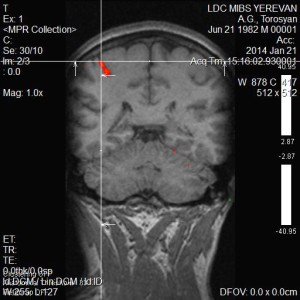

Նկարներում պատկերված է ձախ ձեռքի շարժիչ կենտրոնը, այն գտնվում է աջ կիսագնդի առաջկենտրոնական գալարում:

Ֆունկցիոնալ ՄՌՏ գնահատում է ուղեղի նեյրոնալ ակտիվության հետևանքով առաջացած հեմոդինամիկ փոփոխությունները, որի շնորհիվ հնարավոր է դառնում մեծ ճշգրտությամբ առանձնացնել ուղեղի կենտրոնները (խոսքի, տեսողության, շարժիչ և այլն): Չխորանալով մեթոդի ֆիզիկական սկզբունքների մեջ նշենք, որ ֆՄՌՏ-ի շնորհիվ կարելի է խուսափել կամ գոնե կանխատեսել հետվիրահատական նյարդաբանական դեֆիցիտները: Նախկինում նույնիսկ ամենաշնորհալի նյարդավիրաբույժները չէին կարողանում պատասխանել հիվանդների հարցերին, կապված հետվիրահատական բարդությունների հետ: Դա առաջին հերթին պայմանավորված է անատոմիական յուրահատկություններով, հարկ է նշել, որ պացիենտների գլխուղեղի ֆունկցիոնալ զոնաները լրջորեն կարող են տարբերվել բժշկական համալսարաններում օգտագործվող անատոմիական ատլասներում ներկայացված գլխուղեղի զոնաներից: Հետևաբար վիրաբույժի աչքի համար անտեսանելի կենտրոնները շատ հաճախ վնասվում էին և վիրահատությունից հետո պացիենտները դժվարանում էին ինքնուրույն տեղաշարժվել, կորցնում էին ինքնասպասարկման տարրական ունակությունները, խոսքի կարողությունը: